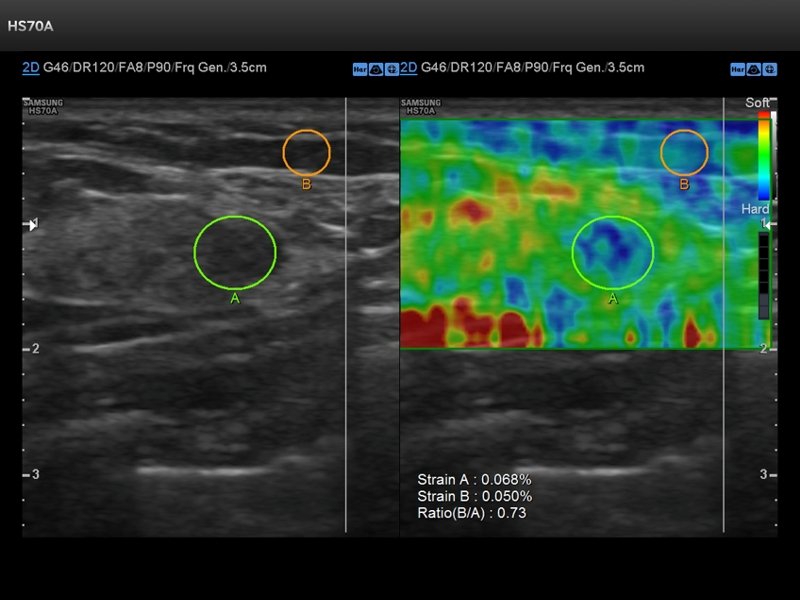

Breast elastography is an advanced ultrasound technique that measures the stiffness or elasticity of breast tissue. Since cancerous tissues are usually firmer than normal tissue, elastography helps in distinguishing benign (non-cancerous) from suspicious breast lumps. It is often used as an additional tool along with routine breast ultrasound and mammography.